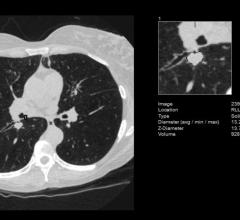

September 14, 2022 — An AI tool is highly effective at detecting pancreatic cancer on CT, according to a study published ...